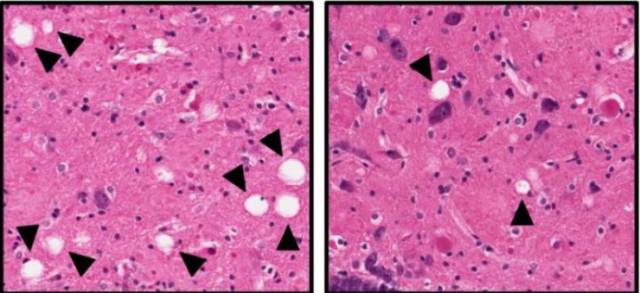

安慰剂大鼠(左)大脑出现了严重的神经损伤(箭头所指空泡代表坏死的神经组织)而接受P7C3治疗的大鼠损伤显著降低(右)

不仅如此,当Pieper教授在24个月时对两组大鼠的大脑组织进行组织病理学检查以及淀粉样沉积物,Tau蛋白磷酸化,神经炎症标志物检查。结果发现,P7C3并没有改变大鼠脑内这些所谓的“阿尔兹海默病标志物”的堆积,即这些标志物在两组大鼠脑内的堆积状况是相同的。也就是说,即使存在早期的阿尔茨海默病病理事件,例如淀粉样蛋白积累,神经纤维缠结和神经炎症,P7C3仍旧具有强大的保护神经损伤功能,并且这一治疗方案仍能带来明显的临床益处。